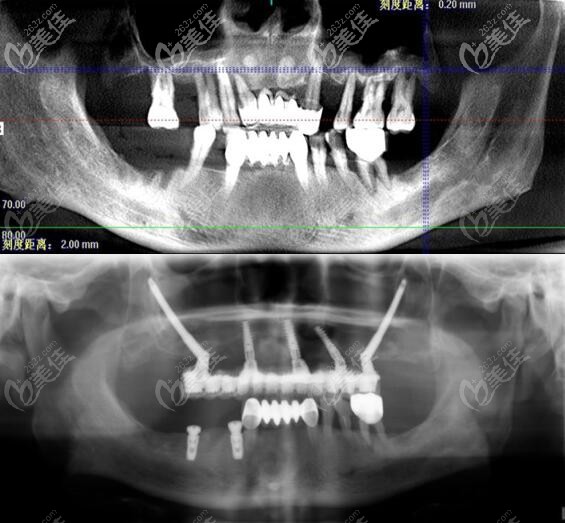

王明院长拿手的穿颧种植牙手术▼